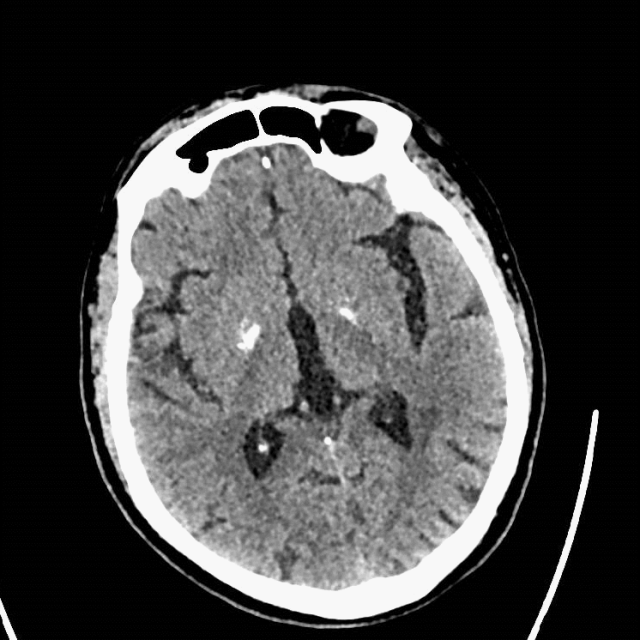

术后复查:颅脑CT平扫未见明显新增脑梗塞。

什么叫桡鞘【例久弥新】寻道于桡——瑞康通5.5F Introsky X导管鞘经桡取栓一例_https://www.jmylbn.com_新闻资讯_第28张

什么叫桡鞘【例久弥新】寻道于桡——瑞康通5.5F Introsky X导管鞘经桡取栓一例_https://www.jmylbn.com_新闻资讯_第29张

复查颅脑CTA及CTP,改善明显。